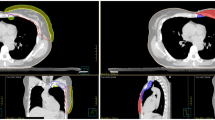

As shown in Fig. 1 isodose distribution ranges from 5 Gy to 44 Gy for a selected case under breath-hold conditions. Here the conformal dose coverage of 95% PD to PTV was observed for VMAT and hybrid plans, compared to the 3DCRT plan, which showed a higher spread of dose coverage outside the PTV. The 5 Gy isodose area was shown to account for low dose spill, which looks spread over a larger area in VMAT in comparison with 3DCRT hybrid plans. In addition, it is observed from graphical representation (Fig. 3) of body segments receiving low dose spill of 2 Gy, 5 Gy and 10 Gy are considerably higher in VMAT than 3DCRT (> 50%) and hybrid (> 30%). Although the 2 Gy dose spill were seen higher in hybrid plans (50%) than 3DCRT, 5 Gy (28%) and 10 Gy (4%) spill were almost comparable. To find a better-quality plan, various dosimetric matrices for PTV were analyzed, as listed in Table 3. According to that, the VMAT showed a higher dose coverage to Total PTV, PTVSCF, and PTV-CW/BR by nearly 97% followed by hybrid plans with approximately 95%. However, the dose coverage by 3DCRT were 89.43 ± 4.78%, 74.24 ± 7.63%, and 91.19 ± 4.77% respectively, with p < 0.05 compared to both h-VMAT80/20 and VMAT. In addition, 3DCRT resulted in inferior HI (0.19 ± 0.04) and CI (0.58 ± 0.15) as they deviate much from the ideal value compared to h-VMAT80/20 (HI = 0.13 ± 0.04; CI = 0.72 ± 0.08), VMAT (HI = 0.11 ± 0.04; CI = 0.75 ± 0.09) with p < 0.05. No significant difference was found among the three ratios of hybrid plans for PTV matrices.